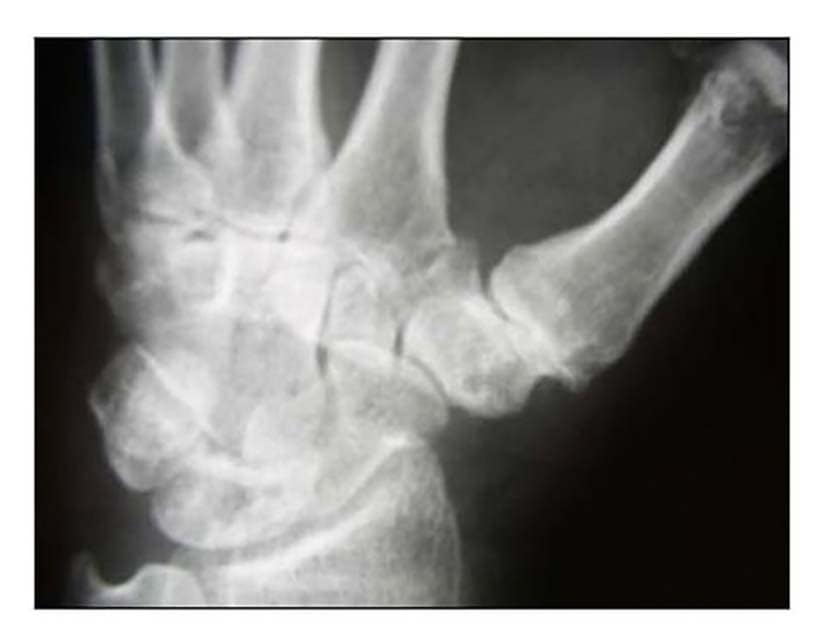

Die Rhizarthrose gehört zum rheumatischen Formenkreis und macht sich je nach Stadium durch eine sehr schmerzhafte zunehmende arthrotische Zerstörung des Daumensattelgelenkes bemerkbar. Nach einer Untersuchung von Pellegrini 1 erkranken Frauen 10- bis 15-mal häufiger an Rhizarthrose als Männer. Das deckt sich mit den Erfahrungen des Autors aus den Evaluierungsübersichten von fast 4.000 Patientinnen und Patienten mit dem durchschnittlichen Verhältnis von 13:1 zugunsten der Patientinnen. Die Rhizarthrose tritt bei Frauen nach den Erfahrungen des Autors ca. 3 Jahre nach dem Beginn der Menopause auf und ist vermutlich genetisch bedingt: Nur zwei Prozent der Patientinnen des Autors erwähnten in der Anamnese, keine Schwangerschaft gehabt zu haben. Auslöser für die Rhizarthrose bei Männern ist in den meisten Fällen eine traumatisch bedingte Verletzung des Daumensattelgelenkes („Skidaumen“) oder eine ständige berufliche Überbeanspruchung, zum Beispiel bei Vibrationen durch Maschinen oder auch durch handschriftliches Schreiben in Büroberufen. Die Rhizarthrose tritt nach Eaton/Littler radiologisch klassifiziert in vier Stadien auf (Abb. 1) 2:

- Stadium I: normale Gelenkkonturen, erweiterter Gelenkspalt (Erguss)

- Stadium II: geringe Gelenkspaltverschmälerung, evtl. vorhandene Gelenktrümmer kleiner als 2 mm

- Stadium III: sklerotische und zystische Veränderungen im subchondralen Knochen, Osteophyten größer als 2 mm, Zerstörung des Daumensattelgelenkes, normale trapezioskaphoidale Gelenkfläche

- Stadium IV: zusätzlich zum Verschleiß der trapeziometakarpalen Gelenkfläche degenerative Veränderungen im Bereich der trapezioskaphoidalen Gelenkfläche

Die Patienten geben bereits beim Stadium I Schmerzen beim Pinzettengriff und/oder beim kleinen oder großen Rundgriff an. Häufig treten die ersten Schmerzen beim Schwenken der Daumen zur volaren Handfläche auf. Beim Stadium II treten die Subluxationsstellung im Daumensattelgelenk und eine temporäre Schmerzhaftigkeit bei vielen Tätigkeiten sowie häufig auch in Ruhe auf. Im Stadium III findet sich eine deutliche Luxierung des Daumensattelgelenkes und eine beginnende Proximalisierung des Mittelhandknochens des Daumens. Zusätzlich geben die Patientinnen und Patienten eine Schmerzhaftigkeit auch bei bereits geringen Bewegungen an. Häufig wird auch über Nachtschlafstörungen beim Greifen nach dem Kopfkissen oder dem Oberbett geklagt. Im Stadium IV finden sich ebenfalls eine deutliche Luxierung des Daumensattelgelenkes, eine deutliche Proximalisierung des Daumenmittelhandknochens und eine Schmerzhaftigkeit auch bei bereits geringen Bewegungen. Häufig findet man eine Fehlstellung des Daumens im Daumengrundgelenk. Oft ist zunächst die sekundäre Hand – beim Rechtshänder das linke Daumensattelgelenk, beim Linkshänder umgekehrt – von der Rhizarthrose betroffen. 18 Prozent der versorgten Patienten litten an einer zu versorgenden doppelseitigen Rhizarthrose. Durch einen vom Autor 2010 entwickelten Testgriff – ähnlich dem Ansatz des Daumens beim Händeschütteln – durch Druck des Daumens der Patienten in die Tabatiere des Behandlers kann festgestellt werden, bei welchem Druck der Schmerz einsetzt.